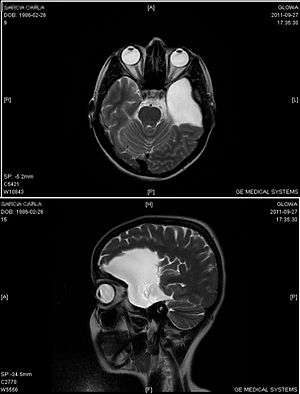

An MRI of a 25-year-old woman with left frontotemporal arachnoid cyst.

Diagnosis is principally by MRI. Frequently, arachnoid cysts are incidental findings on MRI scans performed for other clinical reasons. In practice, diagnosis of symptomatic arachnoid cysts requires symptoms to be present, and many with the disorder never develop symptoms.